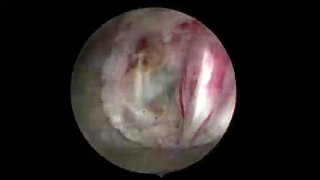

Эндоскопическое удаление металлического осколка из грудного отдела позвоночника